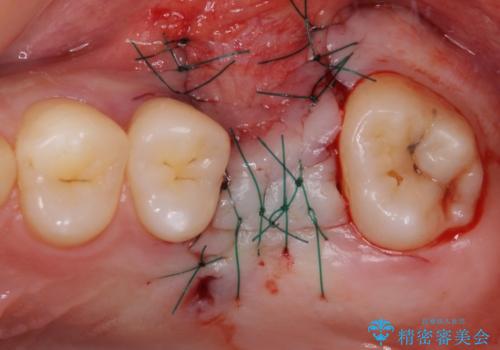

奥歯の虫歯は抜歯が必要であったので、矯正治療前に抜歯をし、矯正治療と並行してインプラントによる補綴治療を行うこととしました。

当院の特徴は、矯正治療とインプラント補綴治療の担当医が同じ歯科医師であるため、両方の治療を並行して行うことができます。